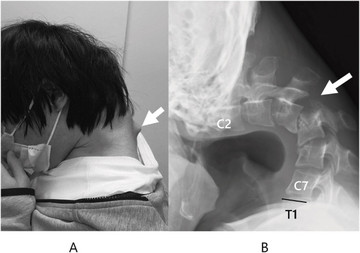

Αποτέλεσμα αυτής της στάσης ήταν να αναπτυχθεί ένα εξόγκωμα στον αυχένα, ενώ ο ίδιος έχασε πλήρως την ικανότητα να σηκώνει το κεφάλι του. Η κάμψη ήταν τόσο προχωρημένη, που το πηγούνι του ακουμπούσε μόνιμα στο στήθος.

Το 2023, ο νεαρός άρχισε να υποφέρει από αφόρητο πόνο στον αυχένα και δυσκολία στην κατάποση, η οποία προκάλεσε ταχεία απώλεια βάρους. Οι ιατρικές εξετάσεις αποκάλυψαν έντονη παραμόρφωση των αυχενικών σπονδύλων, καθώς και βλάβη στην ανώτερη σπονδυλική στήλη – συνέπειες της μακροχρόνιας καταπόνησης και υπερέκτασης των μυών του αυχένα.